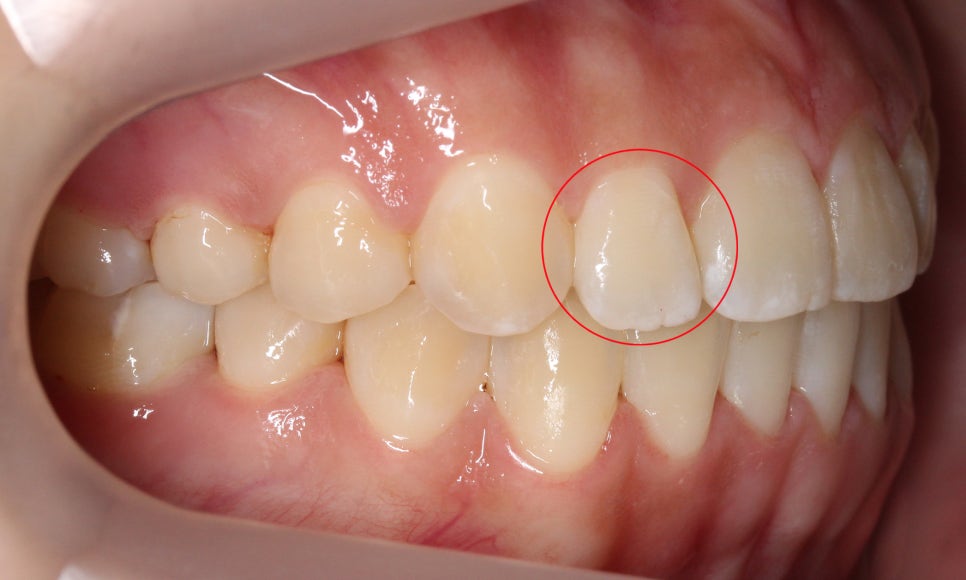

이렇게 환자분의 작은앞니(측절치)처럼

치아 끝이 울퉁불퉁하게 남아 있는 모습을

확인할 수 있는데요,

일반적인 경우 마멜론(톱니치아)은

시간이 지나면서 치아 끝이 마모되어

사라지게 됩니다.

그러나 환자분처럼 치아의

교합 상태가 좋지 않거나

왜소치로 인해 치아 끝이

마모되지 않는 경우

성인이 된 이후에도

마멜론이 남아있기도 합니다!

작은앞니(측절치)의 길이가

짧아 아랫니에 닿지 않는 모습입니다.

환자분의 Case는 왜소치로 인한

마멜론으로 볼 수 있겠죠?

반대쪽 측절치 역시

길이가 짧아서 치아 끝이

거의 마모되지 않은 모습입니다~